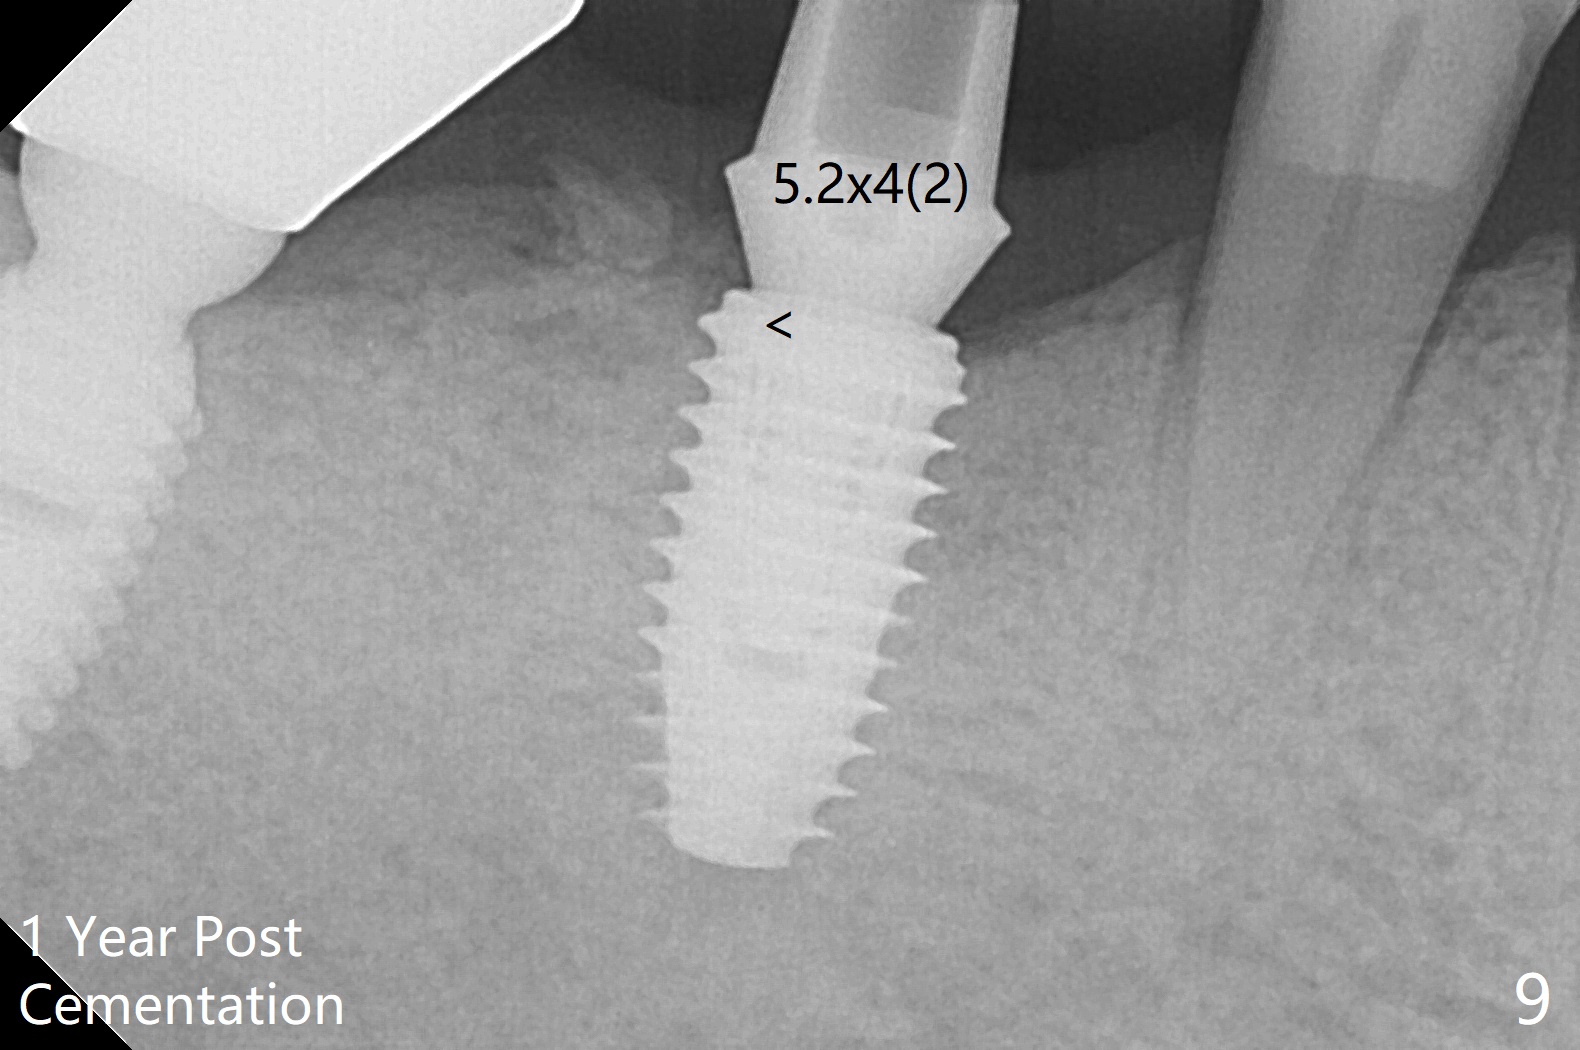

M

Vertical fracture of the mesial root of the tooth #30 after RCT is associated with bone loss (Fig.00 *). When the mesial portion of the mesial root (M', loose one) is exfoliated, the bone loss resolves (Fig.0). To reduce heat-induced bone necrosis at #19, osteotomy is conducted slowly with copious irrigation with cold saline. Bone density is felt while a 5x10 mm implant is being placed after using cortical tap to the 2nd line of the implant driver. The implant needs to be reverse torqued several times before reaching its final depth (Fig.1 (~50 Ncm)). Since the residual roots are superficially positioned, the immediate implant looks as a delayed one. Although the implant is placed mesial to the septum clinically, its position in X-ray seems to be normal. Because of severe wear and lack of vertical height, a 6.8x5 mm healing abutment is placed. Retention of bone graft (Fig.1 *) is maintained by spreading setting acrylic into the edentulous undercut areas (Fig.2 *). The so called "acrylic dressing" remains in place 3 weeks postop (Fig.8). When it is removed with the healing abutment, the wound heals (Fig.3). Note the limited vertical height. The bone graft placed in the distal socket appears to have been converted to the native bone 3.5 months postop (Fig.4). To reduce severe wear of the natural teeth, the occlusion of the new crown is not heavily decreased (Fig.5). It should be alright considering favorable crown/implant ratio (Fig.6). There is no bone loss 5 months post cementation, although the abutment screw is just retightened (Fig.7). In spite of poor trajectory associated with #18 (Fig.8) and 31 (Fig.7) Bicon implants, the abutments have not been dislodged. For the bruxer, the next implant at #19 with distal root fracture (Fig.8 ^) should be Bicon. The patient complains of food impaction nearly 1 year post cementation. The mesial and distal contacts of #30 crowns are light. When the abutment/crown is removed, there is implant well contamination (food debris). It appears that the previous abutment (5.7x4(2) mm, Fig.6,7) is incompletely seated. When a smaller abutment is placed and torqued at 30 Ncm, it is seated fully (Fig.9 (<: no gap)). New impression is taken. The distal gingival embrasure is larger than the mesial one because of the higher distal crest (Fig.6,7). If there is food impaction distal to the new crown, the distal crestal bone should be removed with lab closure of the embrasure.